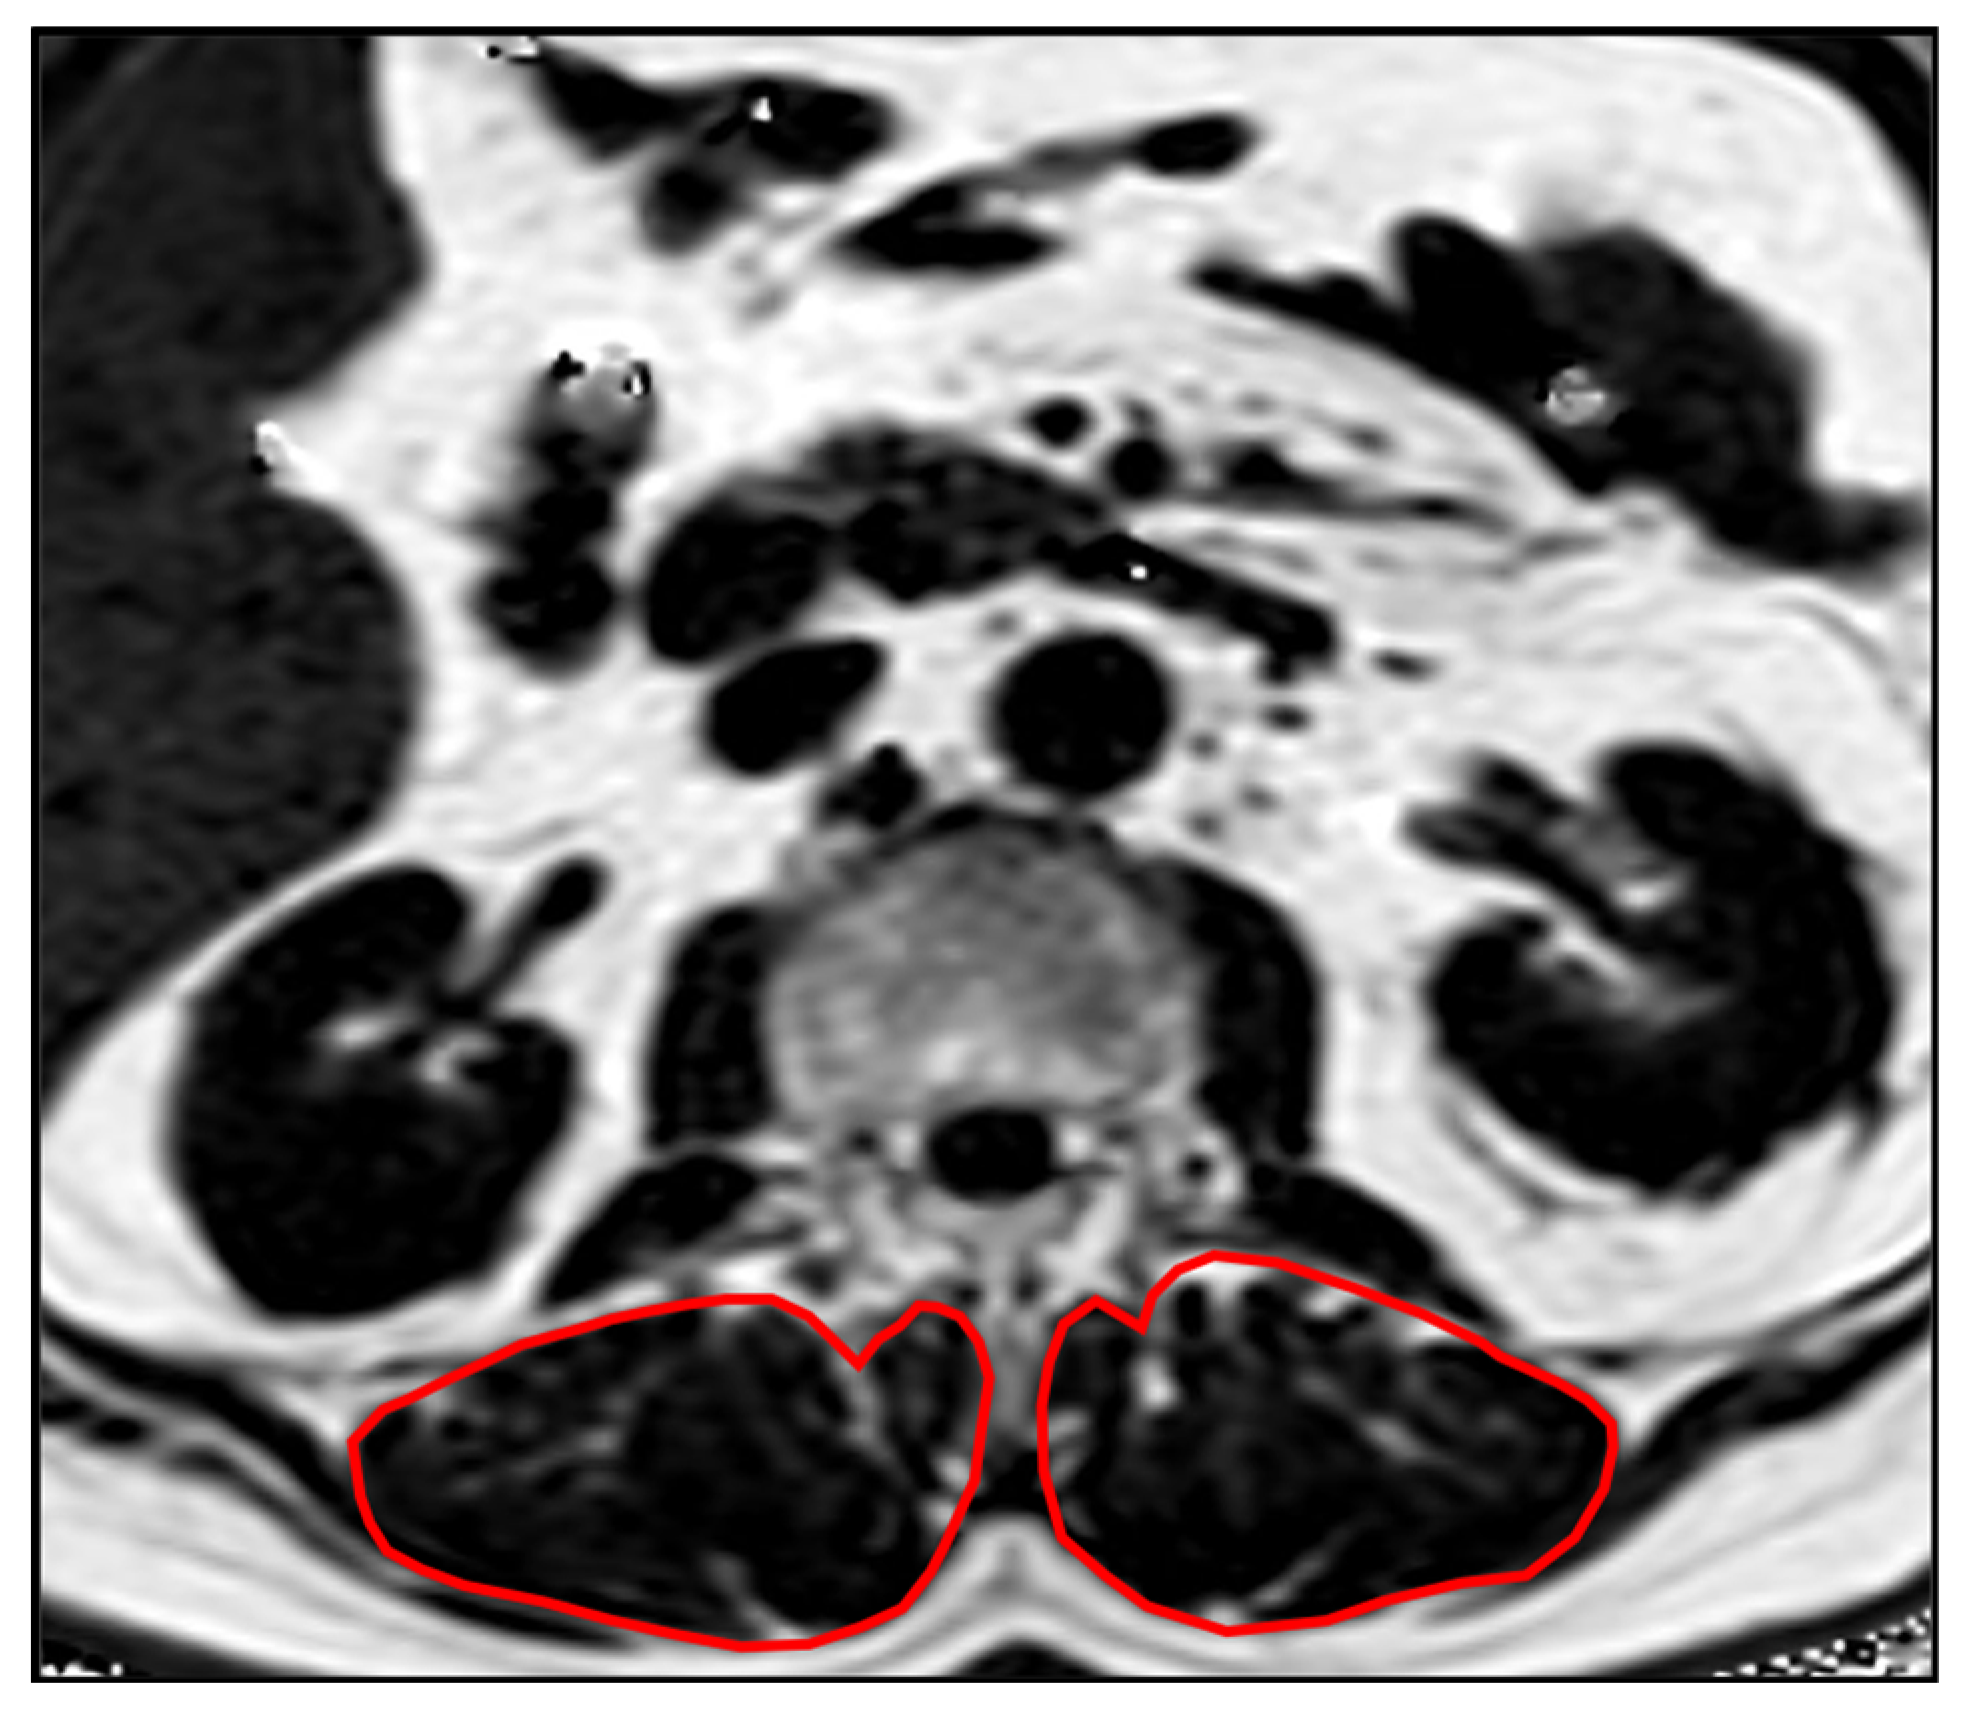

2.4. Paraspinal Muscle and Vertebra Segmentation

- Sollmann, N.; Dieckmeyer, M.; Schlaeger, S.; Rohrmeier, A.; Syvaeri, J.; Diefenbach, M.N.; Weidlich, D.; Ruschke, S.; Klupp, E.; Franz, D.; et al. Associations Between Lumbar Vertebral Bone Marrow and Paraspinal Muscle Fat Compositions-An Investigation by Chemical Shift Encoding-Based Water-Fat MRI. Front. Endocrinol. 2018, 9, 563. [Google Scholar] [CrossRef]